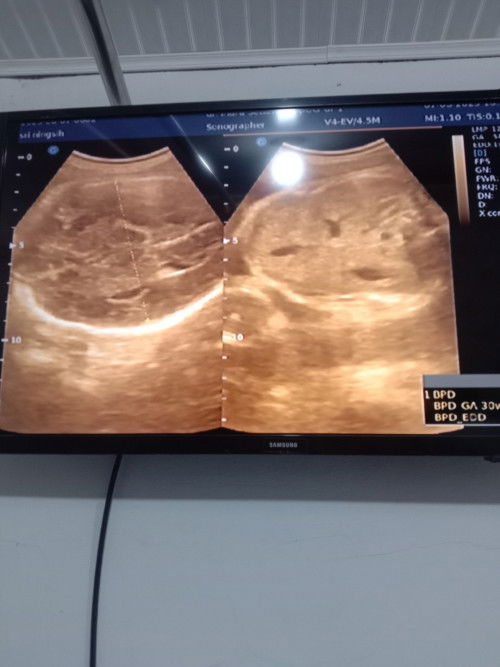

Bunda saya diagnosa plasenta Previa pasial ( plasenta rendah)

Bisa lahiran normal gak ya bunda. Usia kehamilan 34 Minggu kepala sudah dibawah. Saya tidak ada ngeflek tau pendarahan, cuman area kemaluan sering ngilu. Bagi pengalaman ya lah bunda. Anak ke 2 ni bun. Saya takut sekali SC ni.

Bunda saya mau tanya lebih akurat perhitungan terakhir haid apa pemeriksaan USG diawal kehamilan. Soalnya jarak ya lumayan jauh juga dari perkiraan.